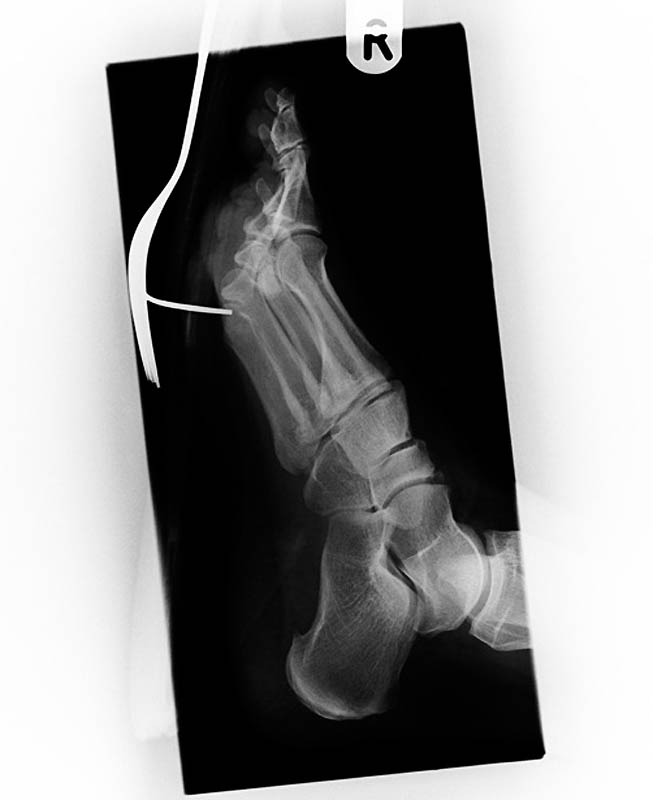

Старинный рентгеновский снимок ступни солдата англо-бурской войны (1899-1902) с огнестрельным ранением. Пуля застряла в плюсневой кости между большим и вторым пальцами